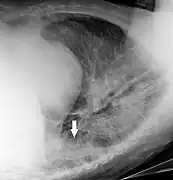

Chest radiographs are used to diagnose many conditions involving the chest wall, including its bones, and also structures contained within the thoracic cavity including the lungs, heart, and great vessels. Conditions commonly identified by chest radiography include pneumonia, pneumothorax, interstitial lung disease, heart failure, bone fracture and hiatal hernia. Typically an erect postero-anterior (PA) projection is the preferred projection. Chest radiographs are also used to screen for job-related lung disease in industries such as mining where workers are exposed to dust.[12]

For some conditions of the chest, radiography is good for screening but poor for diagnosis. When a condition is suspected based on chest radiography, additional imaging of the chest can be obtained to definitively diagnose the condition or to provide evidence in favor of the diagnosis suggested by initial chest radiography. Unless a fractured rib is suspected of being displaced, and therefore likely to cause damage to the lungs and other tissue structures, an X-ray of the chest is not necessary as it will not alter patient management.